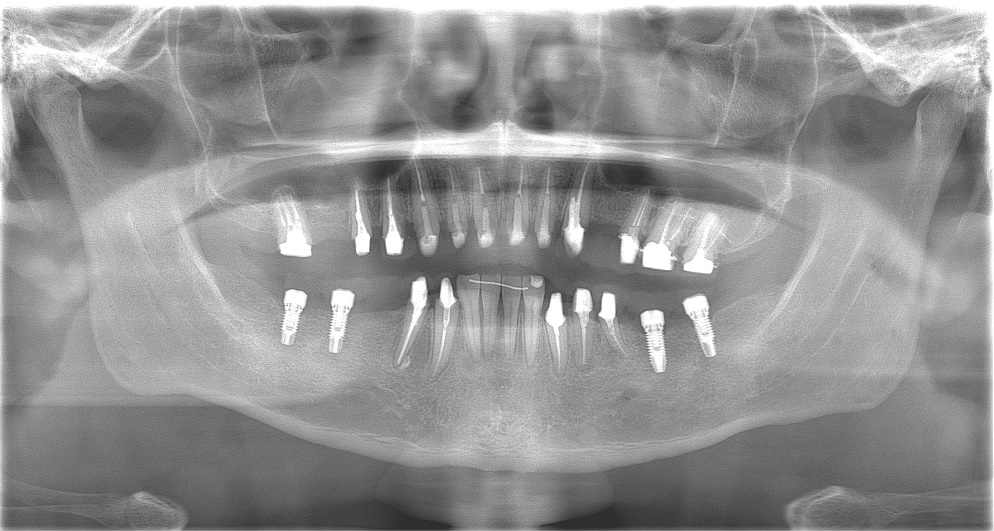

様々なことを鑑み、患者様とも何度も話し合いを行い、下の奥歯には必要最低限のインプラントを、他の歯も外科処置を施しなるべく歯を抜かない方法を取りました。

最終的に抜歯した本数は下の歯5本。上の歯に関しては全て残すことが出来ました。

奥歯があることで前歯の負担を減らし、前歯を失うリスクを下げることが出来ます。